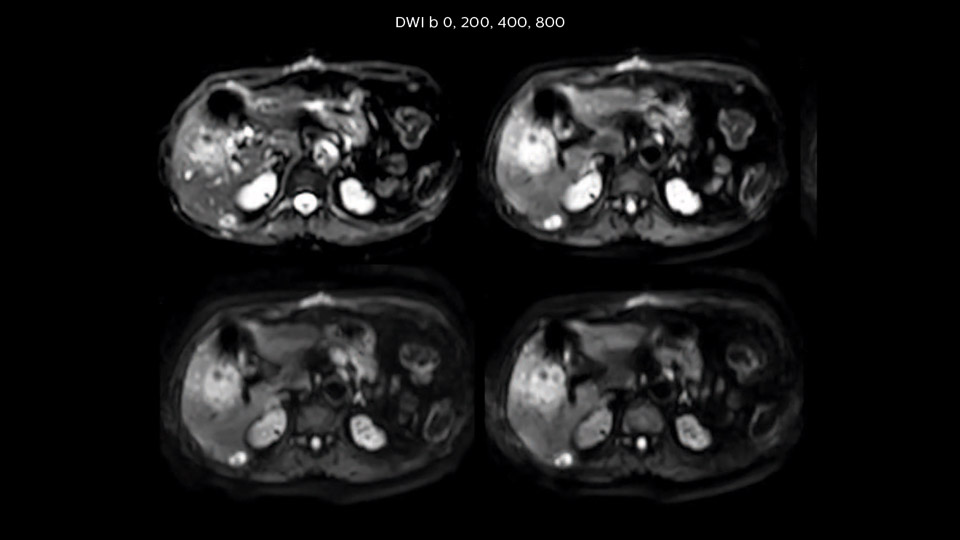

“We acquire one transversal high resolution T2-weighted sequence with 3 mm slice thickness, for example for pancreas or liver lesions. Then we also add a T2 fat suppressed MultiVane XD SPIR sequence. We perform these two routinely in our liver imaging. We use high dS SENSE factors to significantly shorten scan times to 2-4 minutes, which can improve our protocol; it’s a very robust scan.”